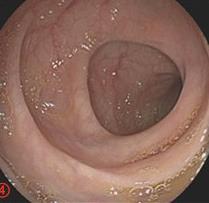

摘要:目的 探讨利那洛肽联合西甲硅油与复方聚乙二醇电解质散(PEG)对便秘患者肠道清洁效果的有效性和安全性。方法 采用前瞻性随机对照试验,通过单盲法,纳入2023年4月-2024年8月于该院消化内镜中心行结肠镜检查的便秘患者383例,随机分为常规组(128例)、实验A组(128例)和实验B组(127例)。常规组采用3 L PEG(Ⅰ)溶液,实验A组采用290 μg利那洛肽 + 2 L PEG溶液,实验B组采用290 μg利那洛肽 + 30 mL西甲硅油+2 L PEG溶液。比较3组患者的肠道准备效果[Boston肠道准备量表(BBPS)评分和去泡效果]、病变检出率、首次排便间隔时间、排便次数、盲肠插管成功率、进镜时间、退镜时间、不良反应发生率和重复检查意愿等。结果 3组患者BBPS评分比较,差异无统计学意义(P > 0.05);实验B组的去泡效果评分明显低于常规组和实验A组,差异均有统计学意义(P < 0.05);实验B组的病变总检出率和息肉检出率明显高于常规组和实验A组,差异均有统计学意义(P < 0.05);常规组的首次排便间隔时间明显长于实验A组和实验B组,差异均有统计学意义(P < 0.05);3组患者排便次数比较,差异无统计学意义(P > 0.05);3组患者盲肠插管成功率均为100.0%,进镜时间相当,差异均无统计学意义(P > 0.05);实验B组的退镜时间明显短于常规组和实验A组,差异均有统计学意义(P < 0.05);常规组腹胀腹痛发生率和不良反应总发生率明显高于实验A组和实验B组,差异均有统计学意义(P < 0.05);常规组重复检查意愿率明显低于实验A组和实验B组,差异均有统计学意义(P < 0.05)。结论 290 μg利那洛肽联合30 mL西甲硅油与2 L PEG溶液方案在便秘患者肠道准备上具有优势,较3 L PEG溶液和290 μg利那洛肽+2 L PEG溶液方案,可获得更好的肠道清洁效果,且安全性和患者重复检查意愿率高,可作为便秘患者肠道准备的推荐方案。